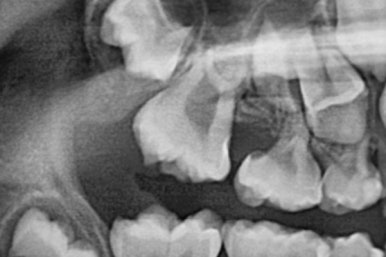

7개월 뒤 사진입니다.

해당 부위 어금니가 약간 나왔씁니다. 가장 간단하게 치료를 할 수 있는 상황이 되었네요.

매우 운이 좋았던 경우입니다.

장치를 부착했습니다.

할터만 장치(Halterman)는 굉장히 간단한 컨셉의 장치인데 매우 효율적입니다.

앞쪽 치아에서 반지처럼 둘러싸고 이를 이용해 어금니를 뒤로 쭈욱 당겨주면 끝.

어금니 방향이 서서히 변해가는 것을 보실 수 있을 것입니다.

단 3개월만에 제대로 못나오던 어금니 위치가 바로 잡혔습니다.

왼쪽이 부산어린이치아교정 키다리아저씨치과에서 치료하기 전 사진, 오른쪽이 후 사진입니다.

어금니가 잘 나온것을 확인할 수 있습니다.

왼쪽이 부산어린이치아교정 시행 전 X-ray, 오른쪽이 시행 후 X-ray 입니다.

3개월만에 많이 좋아졌습니다.